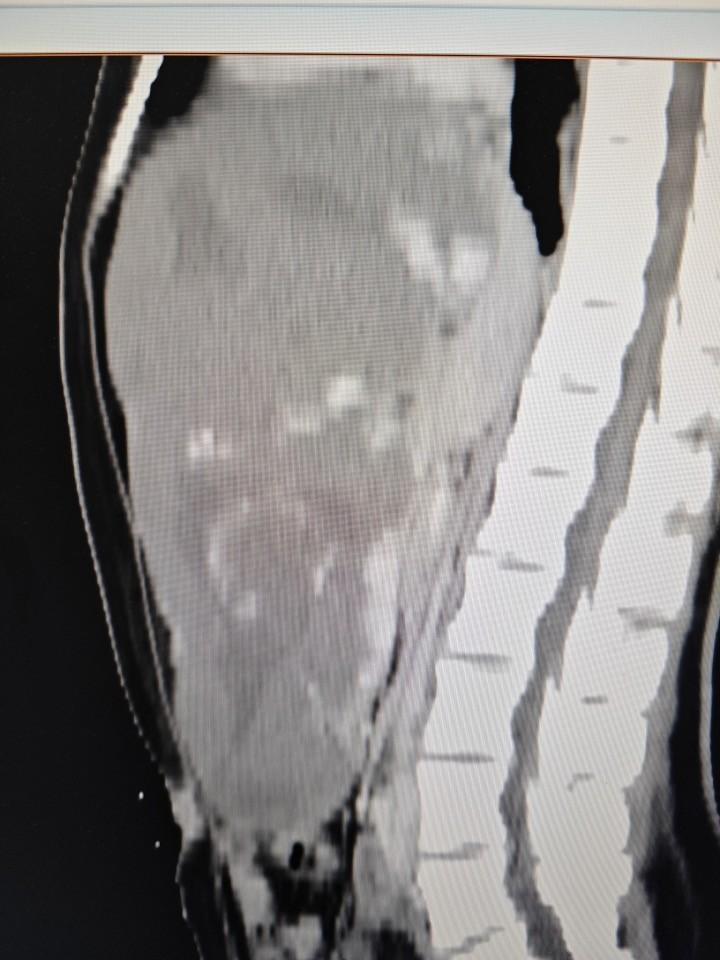

肝脏中常见的良性肿瘤——肝血管瘤,通常不威胁生命健康。但若肿瘤体积增至30cm×24.4cm×14.6cm,则会严重损害血液循环,压迫周边器官,并带来生命危险。李女士的病例生动地体现了这一罕见疾病的典型症状。

肝血管瘤主要因肝内血管过度扩张与生长所致。李女士的肿瘤体积大幅增长,濒临突破常规解剖限制,几乎触及腹腔容量上限。此巨型肿瘤不仅侵占腹腔空间,还对胃、肠等邻近器官施加压迫,不仅损害其功能,更可能引发器官移位或变形,进而加剧患者不适。

经过周密策划与预案审核,由杨诏旭副主任领衔的包括范明、张小晶、郝晓坤、刘海旺等在内的医疗小组,迅速投入到一台极具挑战性的手术中。术中,在患者腹部壁下方成功建立了观察窗,内窥镜观察发现腹腔几乎被巨型血管瘤完全占据。因第一肝门受到严重压迫,手术区域非常狭小。

巨型血管瘤内充血液,外围环绕着丰富的血管网和连接肝组织的分支。手术过程中,需在狭窄空间内细心、准确地逐段辨认并结扎肿瘤周边的血管。此过程对施术者的耐力与精确度极为关键,任何失误都可能导致大量出血。